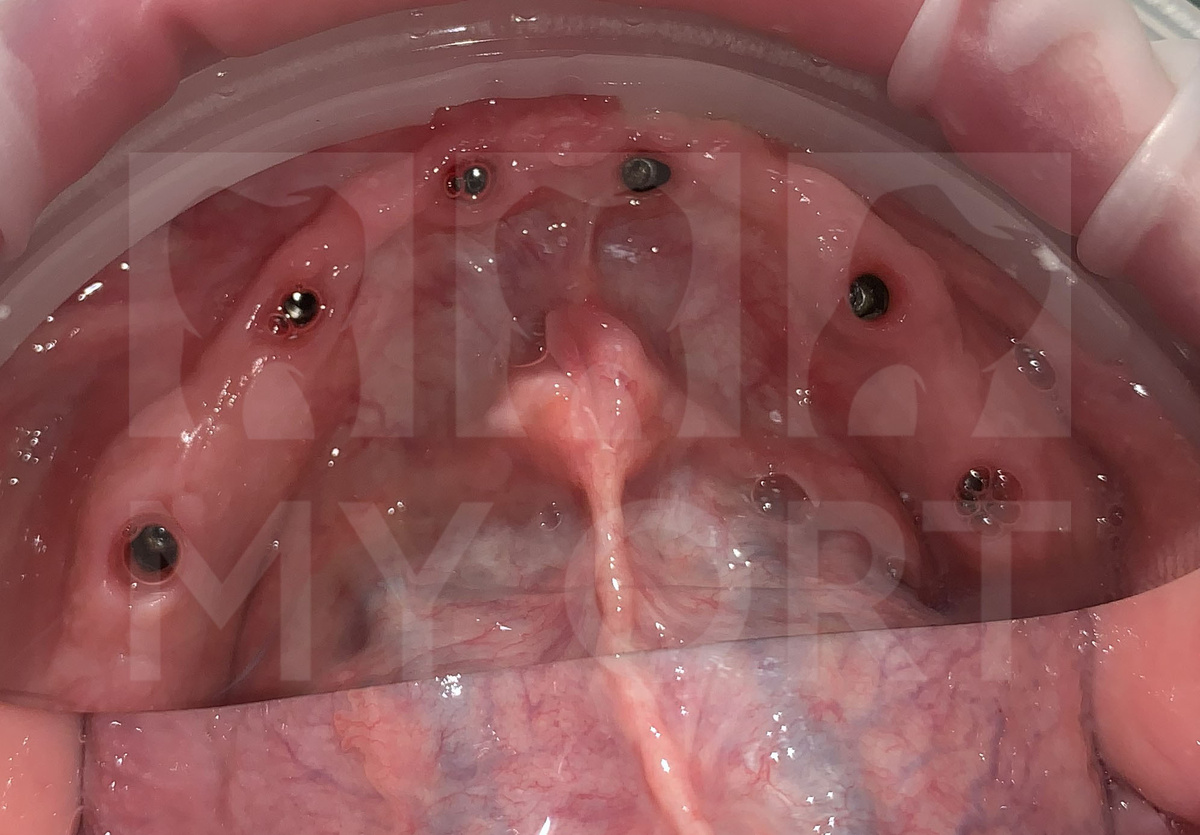

Через 3 месяца после восстановления тканей по согласованию со стоматологом-ортопедом, была проведена установка 5-ти дентальных имплантатов на верхней и 6-ти на нижней челюстях.

Через 3 месяца после имплантации была проведена контрольная компьютерная томография (КТ), которая подтвердила стабильность всех 11 имплантатов.

Были установлены формирователи десневой манжеты (ФДМ) для корректного формирования мягких тканей.

Установка формирователя десны

Формирователь десны (ФДМ) - временная конструкция, устанавливаемая на зубной имплантат после его приживления. Его главная задача в формировании правильного и эстетичного контура десны вокруг имплантата, чтобы будущая коронка выглядела более естественно. Также является промежуточным звеном между имплантатом и постоянной коронкой, помогая заживлению тканей и подготавливая десну к установке протеза.